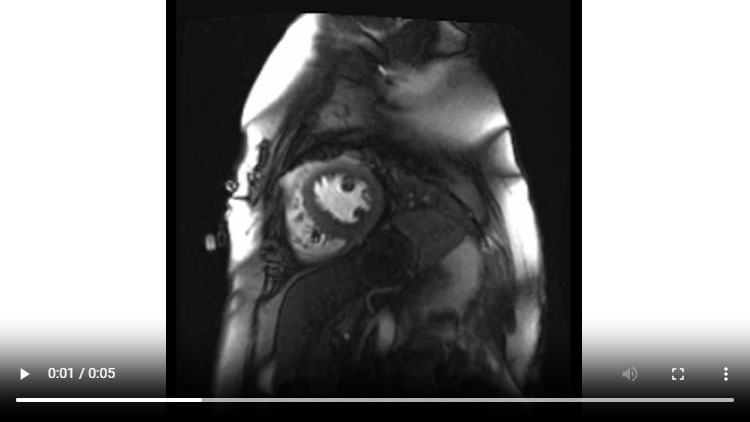

Figure 1A : Séquence Ciné-IRM - Coupes petit-axe basal

- Présence d’une hypertrophie ventriculaire gauche (HVG) asymétrique à prédominance septale mesurée au maximum à 23 mm.

- Visualisation de la sonde de PM avec artéfacts métalliques modérés au niveau du ventricule droit (flèches roses).

- Présence d’un épanchement péricardique de moyenne abondance (flèches rouges).